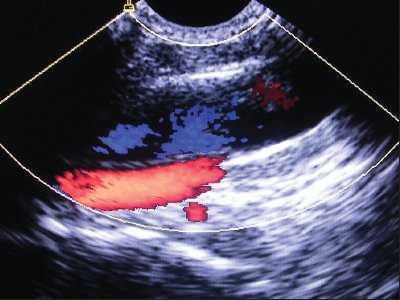

При аномалии размеров отмечалось нормальное расположение внутренней яремной вены и сонной артерии, однако диаметр внутренней яремной вены был меньше диаметра сонной артерии (рис. 4).

Рис. 4. Аномалия размера внутренней яремной вены при ее нормальном расположении (вена меньше сонной артерии и имеет округлый вид).

При аномалии расположения отмечалось обратное расположение сосудов: внутренняя яремная вена находилась более глубоко и медиально по отношению к сонной артерии. Как правило, диаметр внутренней яремной вены при аномалии расположения сосудов был существенно меньше диаметра сонной артерии (рис. 5). Все аномалии имели односторонний характер.

Рис. 5. Аномалия расположения и размера внутренней яремной вены (вена располагается медиальнее артерии, ее размер существенно меньше размера артерии).